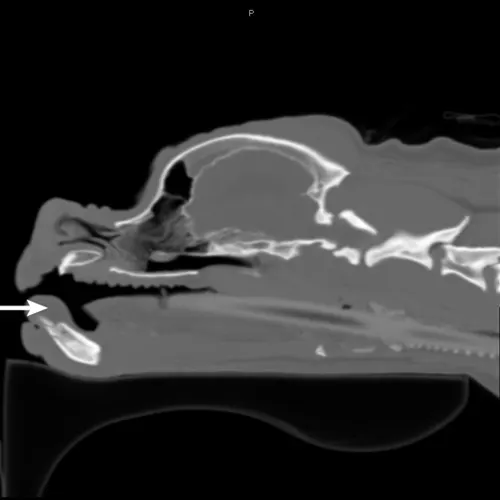

Figure 2

Axial CT image of the head showing an oral mass (arrow) of the rostral mandible. Note the mild lysis of the mandible and widening of the interdental space between the left and right mandibular first incisors.

CBC and serum chemistry profile were within normal limits. Three-view thoracic radiographs were negative for metastatic disease. The patient was anesthetized, and CT of the head and thorax and an incisional biopsy were pursued in the same anesthetic period. The CT scan showed a well-defined, 2.2 x 2.5 x 1.4-cm noncontrast-enhancing, soft-tissue–attenuating mass on the rostral dorsal aspect of the mandible at the level of the incisor teeth, with mild lysis of the mandible and widening of the interdental space at the mandibular symphysis (Figures 2 and 3). The mandibular and retropharyngeal lymph nodes (the most important lymphatic centers for a tumor in this region) and other lymph nodes of the head and neck appeared normal.